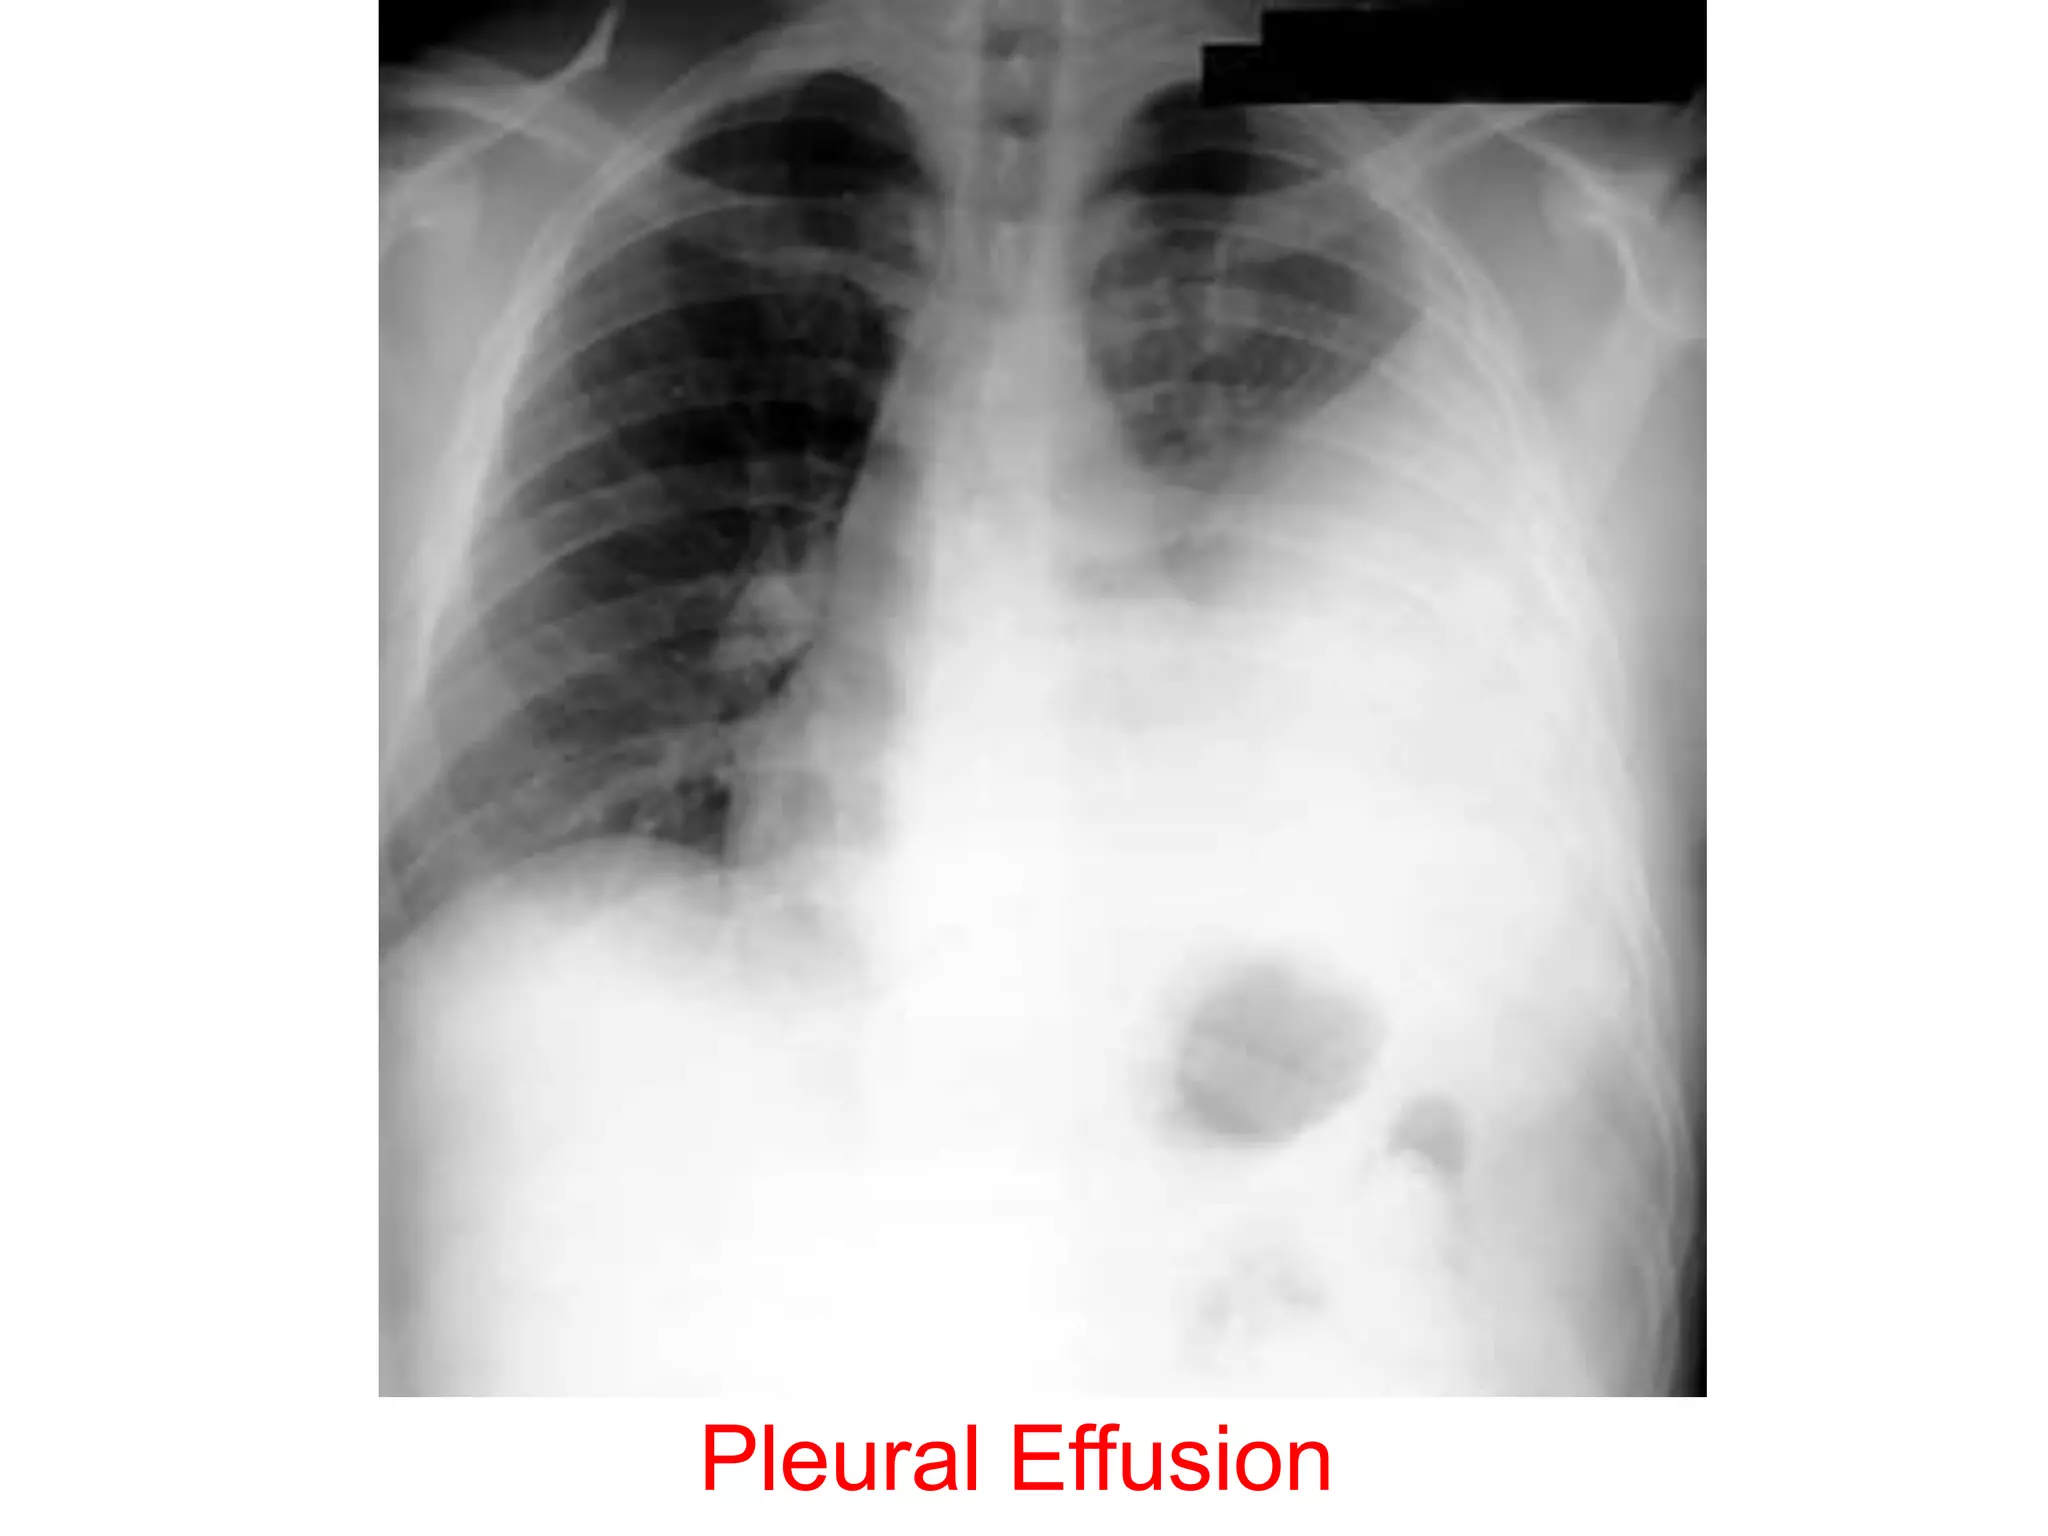

• Chest X-ray PA view showing dense

homogenous opacity at the Rt lung base with

curved upper border, blunting the

costophrenic angle and ascending towards the

axilla. Suggestive of Rt Pleural Effusion

• Around 200 mL of fluid is required in order for

it to be detectable on a PA chest X-ray.

Pleural Effusion

• Figure 10.17

• Chest X-ray showing a

large left pleural effusion

in a young man with a 4-

month history of malaise,

fever, night sweats and

weight loss. The diagnosis

of tuberculosis was

confirmed on histology of

a pleural biopsy and

culture of the pleural

fluid.

• Chest X-rayPA view showing dense homogenous opacity at the Rt lung base with curved upper border, blunting the costophrenic angle and ascending towards the axilla. Suggestive of Rt Pleural Effusion • Around 200 mL of fluid is required in order for it to be detectable on a PA chest X-ray.

• Figure 10.17 •Chest X-ray showing a large left pleural effusion in a young man with a 4- month history of malaise, fever, night sweats and weight loss. The diagnosis of tuberculosis was confirmed on histology of a pleural biopsy and culture of the pleural fluid.